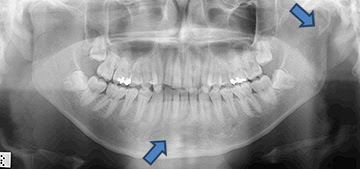

下顎骨骨折 Mandibular Fracture 蔡佩晏醫師的矯正故事 打造你的微笑曲線專家 Dr Tsai S Blog 痞客邦

口腔顎面外科 下顎骨骨折 經典牙醫 大紀元

單純閉鎖性下顎骨骨折 Mandibular Angle Simple Close Fracture 新樓醫院口腔顎面外科的部落格 隨意窩xuite日誌